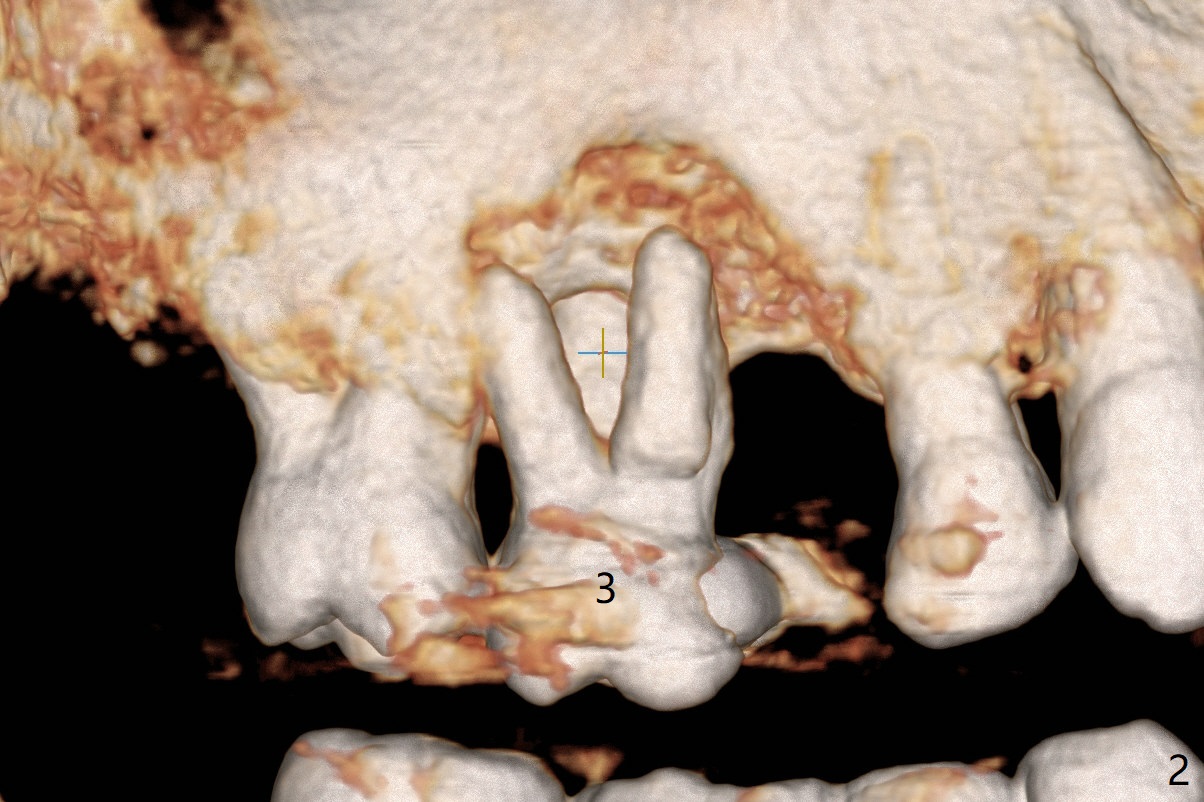

A 49-year-old man (patient of ours for 7 years) has severe bone loss and buccal recession at #3 with missing tooth at #4 (Fig.1,2,5). Short implants will be placed as palatal as possible (Fig.3,4 green) with buccal bone graft (red circles). PRF will be prepared for membranes and sticky bone.